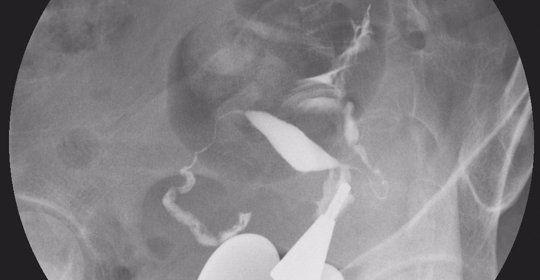

輸尿管造影

輸尿管造影能夠顯示輸尿管的位置、形態以及有無狹窄或阻塞等情況。在X光透視監控下將顯影劑注入體內,然後拍攝前後位及側位片以評估輸尿管情況。可能需要注射對比劑並接受輻射暴露。